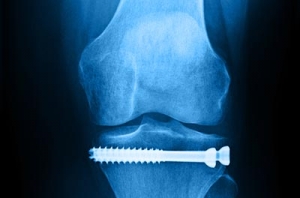

Arbeits- und Schulunfälle, D-Arzt

Unsere Praxis hat die Ermächtigung zur Behandlung von Arbeits- und Schulunfällen.

Jeder Arbeitnehmer, jeder Auszubildende und jedes Schul-, Hort- und Kindergartenkind steht ohne eigenes Zutun unter dem Schutz der gesetzlichen Unfallversicherung. Sie tritt für die Behandlung von Unfällen ein, die sich am Arbeitsplatz, im Betrieb, der Ausbildungsstätte, in der Schule, dem Kindergarten, dem Hort oder der Universität ereignen. Versicherungsschutz besteht auch für den Weg zum Arbeitsplatz und für den Heimweg. Für die Behandlung treten nicht die Krankenkassen ein, sondern die Berufsgenossenschaften.

Da die Leistungen der gesetzlichen Unfallversicherung sehr umfangreich sind, beauftragen die Berufsgenossenschaften bestimmte, von ihnen ausgewählte Ärzte, die sog. Durchgangsärzte oder D-Ärzte, mit der Behandlung ihrer Versicherten.

Für uns als Durchgangsärzte gehört aber nicht nur die Behandlung selbst zu unseren Aufgaben. In Zusammenarbeit mit den Berufsgenossenschaften unterstützen wir die Verletzten auch bei der beruflichen Wiedereingliederung.